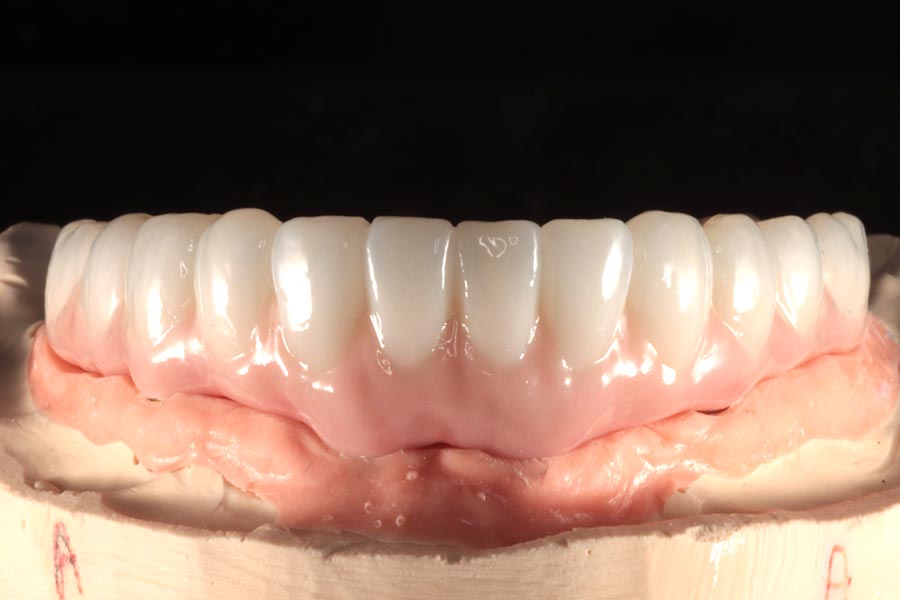

Once the final design is approved, the lab begins fabricating definitive restorations. They are able to add a lot more character and definition at this stage, resulting in restorations that are beautiful and realistic.

More importantly, special care is taken to ensure the tissue-fitting surfaces are smooth and convex. This ensures that any plaque that builds up here is easily removed with regular brushing and water-picking. Hygiene is important for long-term tissue health and this implant success.